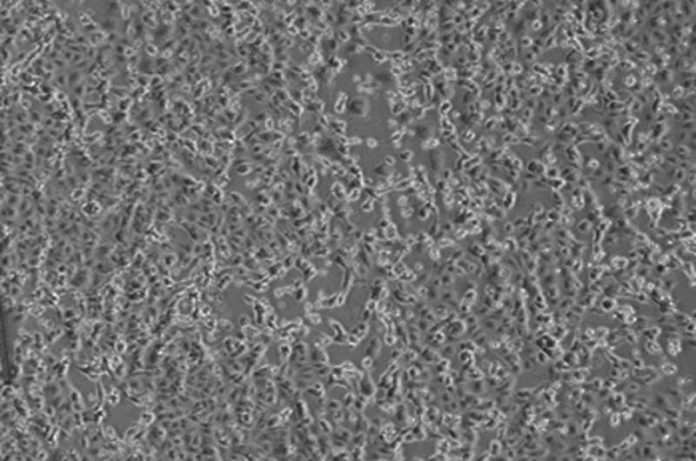

Fot:del virus 2019-nCoV/Italy-INMI1 (Isolamento virale su cellule Vero E6)

I virologi dell’Istituto Nazionale Malattie Infettive “Lazzaro Spallanzani”, a meno di 48 ore dalla diagnosi di positività per i primi due pazienti in Italia, sono riusciti, primi in Europa, ad isolare il virus responsabile dell’infezione. Avere a disposizione in modo così tempestivo il virus è un passo fondamentale, che permetterà di perfezionare i metodi diagnostici esistenti ed allestirne di nuovi. Avere a disposizione nei laboratori il nuovo agente patogeno permetterà inoltre di studiare i meccanismi della malattia per lo sviluppo di cure e la messa a punto del vaccino. La sequenza parziale del virus isolato nei laboratori dello Spallanzani, denominato 2019-nCoV/Italy-INMI1, è stata già depositata nel database GenBank, e a breve anche il virus sarà reso disponibile per la comunità scientifica internazionale.